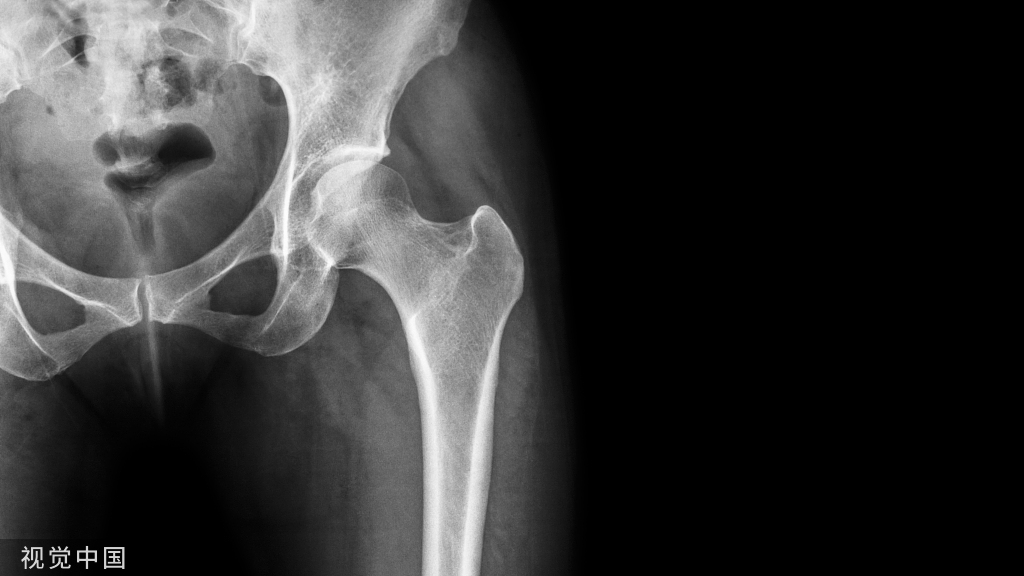

骨质疏松症已被世界卫生组织列为仅次于心血管疾病的第二大危害人类健康的疾病。根据国际骨质疏松基金会发表的一组数据显示:全球每三秒钟就会产生一起骨质疏松性骨折。

骨质疏松症是一种全身性疾病,它的主要特征是骨矿物质含量低下、骨结构破坏、骨强度降低、易发生骨折,是中老年最常见的骨骼疾病。

疼痛、驼背、身高降低和骨折是骨质疏松症的特征性表现。但有许多骨质疏松症患者在疾病早期常无明显的感觉,被称为沉默的杀手。

骨折是骨质疏松症的直接后果,轻者影响机体功能,重则致残甚至致死。